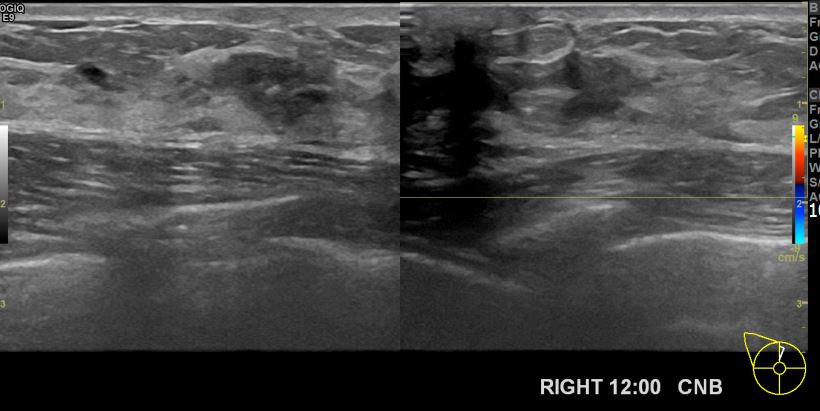

아산유외과개원후 698번째 유방암진단

상기환자 건진상 이상소견으로내원하신 40대 여성분으로 우측유방멍울 조직검사시행후 유방암 진단되었습니다